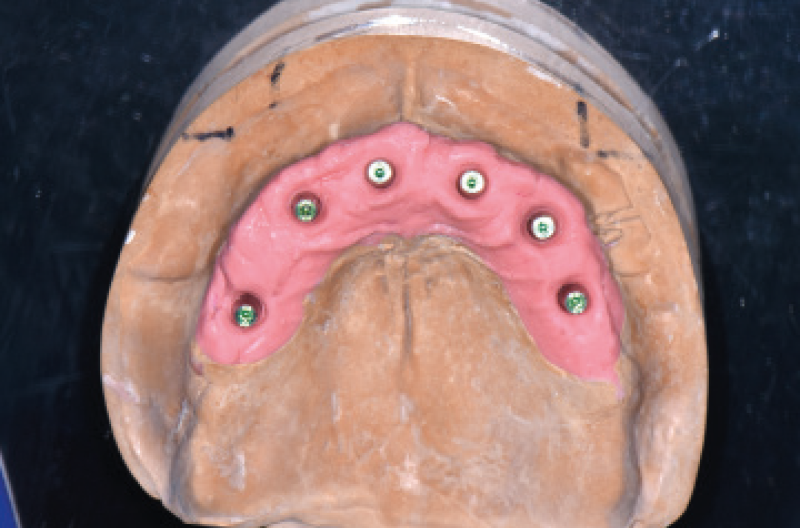

LŌĆÖodontotecnico ha quindi preparato dei modelli di lavoro con gli appositi analoghi – moncone MUA sui quali aveva avvitato gli adattatori Conic. In questa fase lŌĆÖodontotecnico necessita anche di nuove cappette Fixed per tenere conto dei volumi durante la realizzazione delle protesi definitive. Sui modelli di lavoro sono state realizzate delle basi in resina e cera per la registrazione della DV e RC e poi una prova montaggio dei futuri denti seguendo i passaggi della protesi rimovibile. Sono quindi state realizzate due Toronto conometriche con infrastruttura in fibra di carbonio e la parte estetica con denti e porzione gengivale in composito (Figg. 44-51).

Fig. 44 – Modello master inferiore

Fig. 45 – Modello master superiore

Fig. 33 – Adattatori Conic avvitati sui MUA per trasformazione in monconi MUA-Conic

Fig. 34 – Vista occlusale dei monconi MUA-Conic